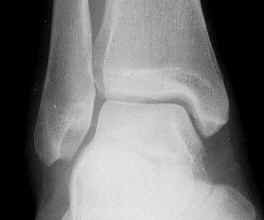

The ankle works in a systematic way. Movement is only supposed to be in one plane, in other words, up and down. We call this dorsiflexion and plantarflexion. The ankle joint is held in place securely by a group of bones that house the main anklebone (called the talus) inside a box-like effect. On the inside is the medial malleolus and on the outside the fibula.

Normal Ankle